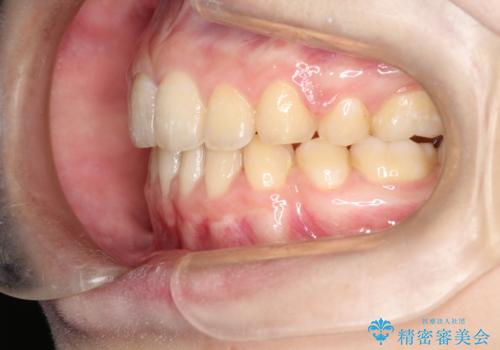

- 口元が出てるのが気になるとのことで来院されました。

歯のがたつきはあまりなかったのですが、口唇が閉じずらく、口元の突出感が確認できました。

上下左右の歯を1本ずつ抜歯して、そのスペースを利用して口元を引っ込める計画としました。

口元を下げて口唇を閉じやすくする場合、抜歯矯正をお勧めさせていただくことが多いです。